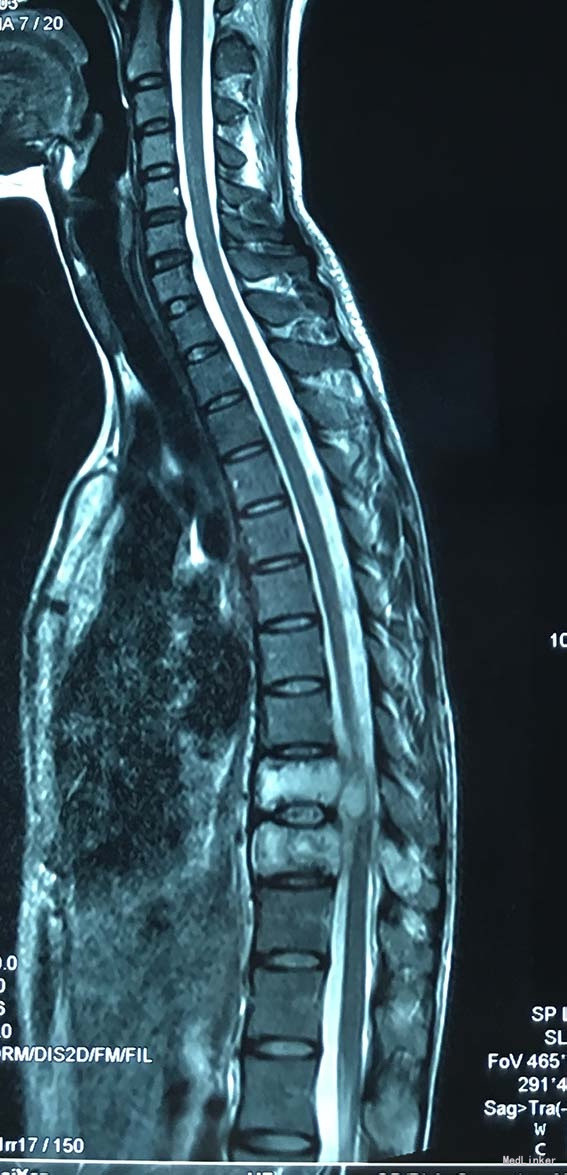

查体:脊柱外观无明显畸形,颈椎活动度正常,胸背部可见纵向长约15cm切口,皮肤钉缝合,伤口愈合可,无红肿渗液。胸椎9-10体左侧棘突旁局部压痛(+)、叩击痛(-),压头试验阴性,双侧侧臂丛牵拉实验(-),双上肢肌张力、运动、感觉及反射无明显异常、躯体感觉无明显减退,双下肢髂腰肌、股四头肌、胫前肌肌力IV级,感觉正常,双下肢直腿抬高试验(-),双侧腱反射对称略活跃,双侧Hoffman征(-),双侧Babinski征(-),双侧髌阵挛(-),踝阵挛(-)。 辅助检查:2015-11外院胸椎MRI检查发现T9-10节段椎体肿瘤并椎旁软组织肿块形成,肿块突入胸腔占位

诊断:胸椎椎体肿瘤(T9-10) 治疗:先于外院行1期后路椎弓根钉固定融合手术,然后转入我院行介入下术前椎体节段血管栓塞手术,第二天行经左侧胸腔入路椎体肿瘤病灶刮除并钛网植骨植入重建手术。术后恢复满意。复查MRI显示肿瘤病灶基本完全切除。